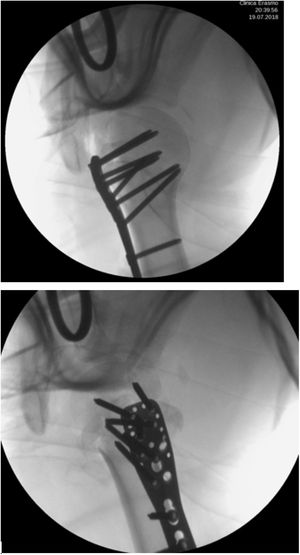

Se realizó reducción abierta de luxación escapulo humeral, osteosíntesis en húmero y reparación del manguito rotador del hombro derecho con una incisión deltopectoral de aproximadamente 20 centímetros que compromete piel y tejido celular subcutáneo; se realiza hemostasia del sangrado a nivel de capas, se hace una disección roma del músculo deltoideo dónde se pudo observar una fractura multifragmentaria de la cabeza del húmero proximal con luxación de la cabeza, se realiza apertura del manguito rotador a través del intervalo de los rotadores entre el subescapular y supraespinoso, disección roma hasta llegar a la cabeza del húmero, se hace reducción abierta de la luxación de la cabeza del húmero. Se realiza reducción abierta de la fractura de humero proximal fijándola inicialmente con 2 clavos Kirschner de 2.0mm, se realiza osteosíntesis con placa de humero proximal 9x3 utilizando 7 tornillos de bloqueo de 3.5mm y 3 tornillos corticales de 3.5mm, se sutura la interface del manguito rotador con suturas Parcus con puntos cruzados, se valora con intensificador de imagen dónde se observa una buena reducción y la cabeza del húmero en posición valga favoreciendo así su fijación (figs. 2 y 3).